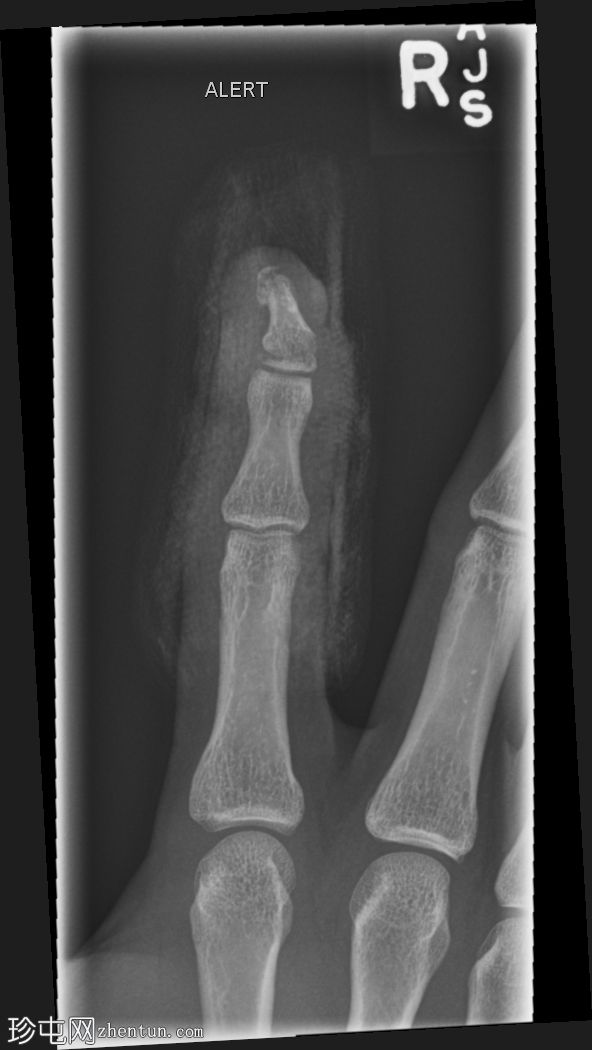

X线片

正位片

右食指远节指骨基底部横向移位骨折,伴有背侧成角,最符合成人型Seymour骨折。指尖小骨折。

本例为罕见的成人型Seymour骨折,此类骨折通常发生于骨骼未成熟的远节指骨骨骺处。